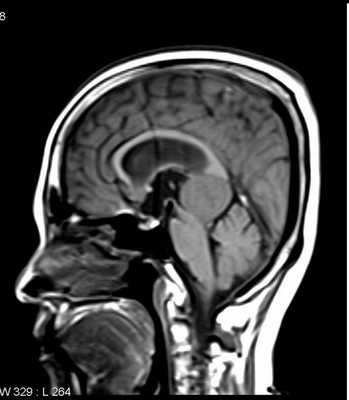

МРТ головного мозга. Субфронтальная менингиома. Сагиттальная Т2-взвешенная МРТ.